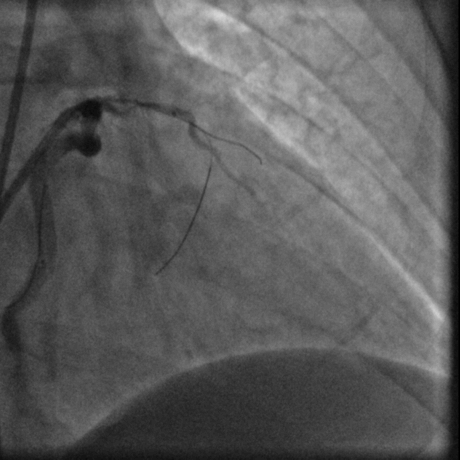

冠脉造影:

蜘蛛位

经右股动脉(8F),送EBU 3. 5指引导管指引导管至左冠开口。Sionblue导丝至LCX保护,Finecross 130到达LCX远端待命。Sionblue引导Corsair 135cm微导管进入LAD。近段纤维帽坚硬(伴钙化随后IVUS证实)尝试使用Gaia1st进入前次假腔,导丝升级Gaia 3rd谨慎前进入间隔支S1,推送corsair进入S1交换KDLC,Pilot 200导丝平行进入LAD真腔。Corsair交换Sionblue到LAD远端。IVUS证实全程真腔,闭塞段以纤维为主。植入支架完成血运重建。